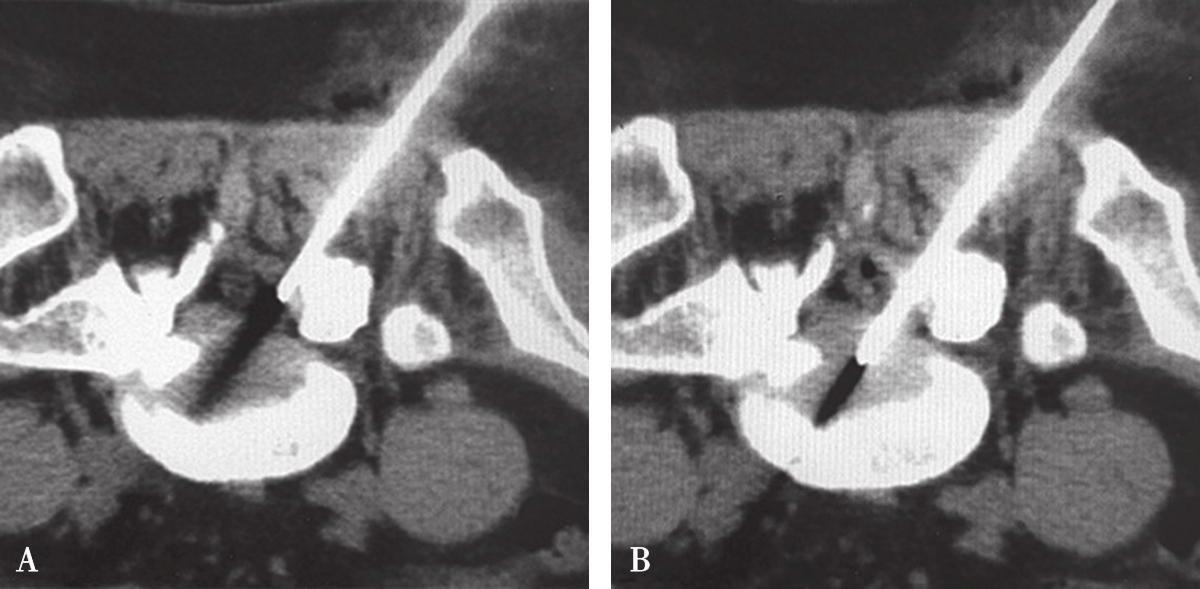

图3-3-24 经椎间孔侧方入路分段穿刺图像

A.目测下部分进针;B.调整方向穿刺到位

图3-3-25 经椎板间隙入路分段穿刺图像

A.椎管外调整好方向;B.椎管内一次穿刺成功

采取分段穿刺技术、借助CT适时扫描、监测矫正定位针位置才是保证安全无误的金标准。所谓分段穿刺技术是按照设计的手术入路,先在安全深度内目测下部分进针,根据CT扫描图像结果调整进针方向直至成功(图3-3-24、图3-3-25)。